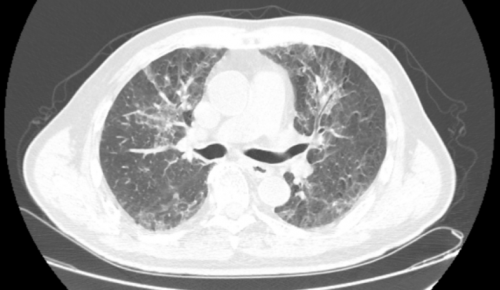

入院时肺部CT(11-07)